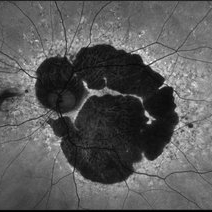

Late Stage Stargardt's Disease

Late Stage Stargardt's Disease

Mar 13 2013 by Hamid Ahmadieh, MD

Autofluorescence imaging of the left eye of a 46-year-old man with decreased VA due to advanced Stargardt's disease.

Photographer: Nayereh Hadipoor, Negah Eye Center, Tehran

Imaging device: Heidelberg Spectralis

Condition/keywords: autofluorescence imaging, Stargardt disease